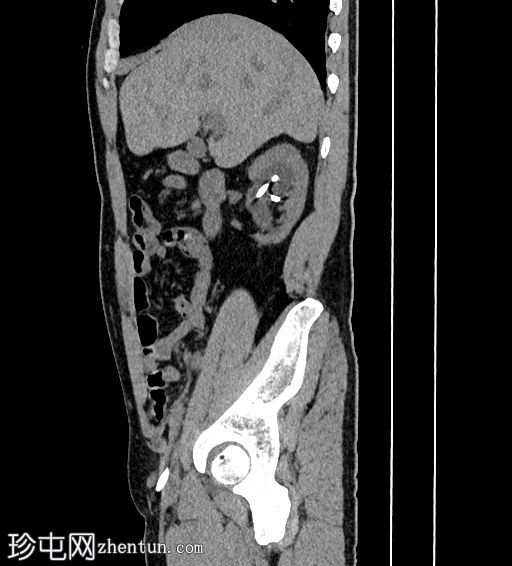

矢状位

平扫

可见中度右肾积水和输尿管积水。右肾双极长10.6厘米。可见输尿管支架,近端位于肾上极肾盏,远端位于膀胱内。肾下极可见肾结石。肾下极可见肾皮质囊肿,囊壁薄,内含钙化。肾上极可见肾实质钙化。在支架旁远端输尿管(S1至S2椎体水平)可见少量输尿管结石。

左肾双极长9.2厘米。肾上极和肾下极可见微小结石。未见输尿管结石。无肾积水或输尿管积水。肾上极可见肾皮质囊肿。

膀胱轮廓正常。未见膀胱结石。